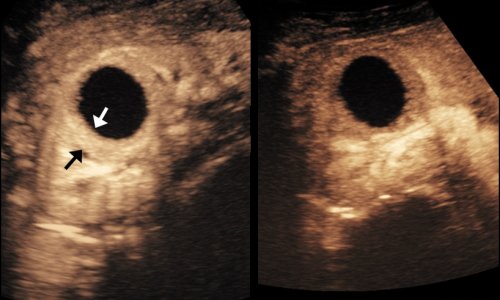

Das Konzept sieht einen systematischen Schallkopf-Rundgang durch den Bauch des Patienten vor. Dabei berücksichtigt der Untersucher bestimmte richtungweisende Veränderungen, die per Ultraschall gut und sicher zu erkennen sind. Neben auffälligen Ansammlungen von Flüssigkeiten oder Luft sind dies vor allem krankhafte Erweiterungen von flüssigkeitshaltigen Hohlorganen. So kann etwa der Harntrakt im Rahmen einer Harnsteinkolik oder der Gallentrakt im Fall einer Gallensteinkolik erweitert sein. Findet der Untersucher auffällig erweiterte Darmschlingen, tastet er sich mit dem Schallkopf an den Ort heran, an dem der Darm verschlossen oder geplatzt ist.

Bowel Obstruction: Sonographic Evaluation

A. Hollerweger, M. Wüstner, K. Dirks

Ultraschall in der Medizin 2015; 36 (03): 216-238, Georg Thieme Verlag, Stuttgart